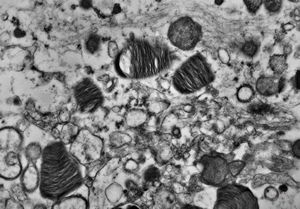

M, 6m. | Niemann-Pick disease - liver

M, 6m. | Niemann-Pick disease - brain